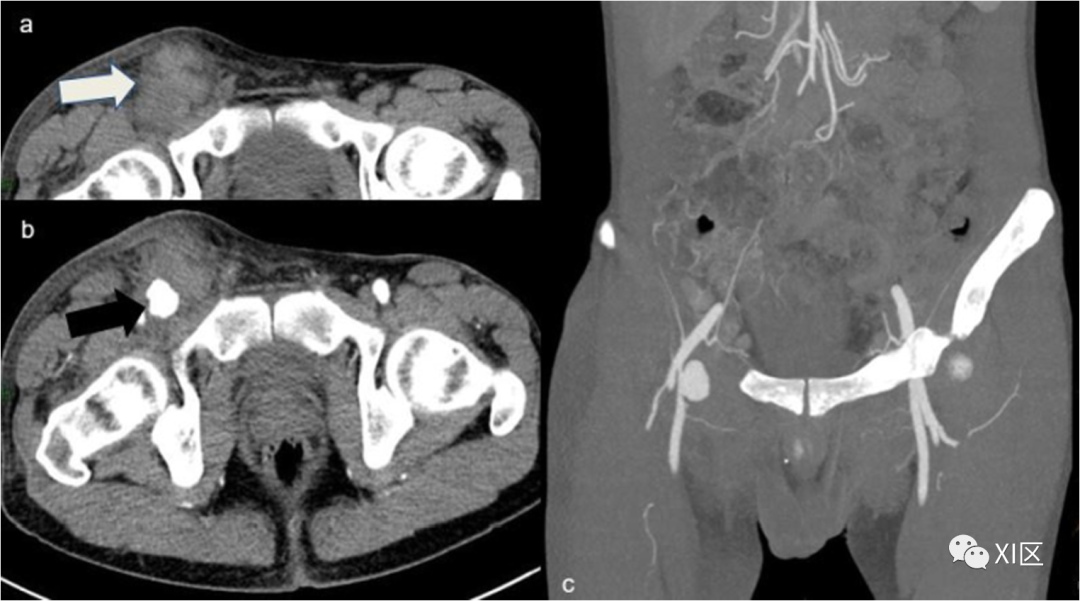

假性动脉瘤(图12)是由动脉壁层的不完全破裂引起的,在CTA中,血管附近有圆形的、清晰的造影剂积聚,可以很容易地与活动性出血区分开来,因为它们是不规则的腔内造影剂池,而且,与持续出血不同的是,假性动脉瘤中的造影剂积聚在延迟期采集时不会发生大小变化。

图12 假性动脉瘤。37岁吸毒男性患者,在穿刺注射药物后出现搏动性腹股沟肿块,进行CTA检查。右侧腹股沟的轴位平扫图像显示腹股沟血肿(白色箭头)。b 右腹股沟动脉期图像,显示清晰的血管外对比剂积聚(黑色箭头)。在MIP重建(c)中,来自右股浅动脉的成分来源非常明显,并确认了假性动脉瘤的诊断。